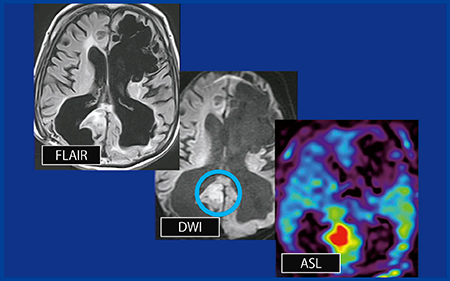

症例7(図7)は,びまん性脳損傷,リンパ腫の既往がある症例で,リンパ腫の再発が疑われて検査を行った。FLAIRでは不明瞭であり,DWIではわずかに高信号領域が認められた(○)。本症例では造影検査ができなかったためASLを追加したところ,DWIと一致して高値を示したことから,リンパ腫の再発であると診断できた。

図7 症例7:PCNSL